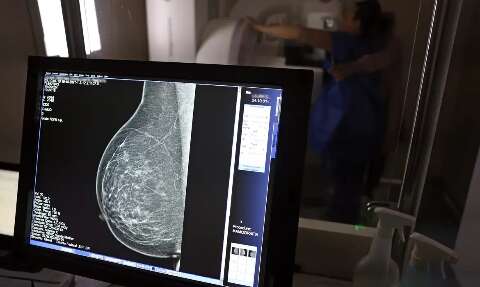

Campo Grande recebe carreta do SUS que fará 60 exames de câncer de mama por dia

A carreta do programa Agora Tem Especialistas, do Ministério da Saúde, começou os atendimentos nesta sexta-feira (10), em Campo Grande, com foco na prevenção e no diagnóstico precoce do câncer de mama e de colo do útero. A unidade permanecerá na capital durante todo o mês, com média de 60 exames diários, entre mamografias e coletas do exame preventivo, mediante triagem e agendamento pelo SUS (Sistema Único de Saúde).

A carreta do programa federal "Agora Tem Especialistas" iniciou atendimentos em Campo Grande nesta sexta-feira, oferecendo exames preventivos de câncer de mama e de colo do útero. Instalada no estacionamento do Hospital do Amor, no bairro Aero Rancho, a unidade móvel realizará cerca de 60 exames diários durante todo o mês. A iniciativa integra as ações do Outubro Rosa e faz parte de um conjunto de medidas do governo federal para ampliar o acesso a serviços especializados do SUS. O programa está presente em 15 municípios de 11 estados, com previsão de realizar 130 mil procedimentos em outubro, incluindo atendimentos a mulheres indígenas e comunidades rurais.